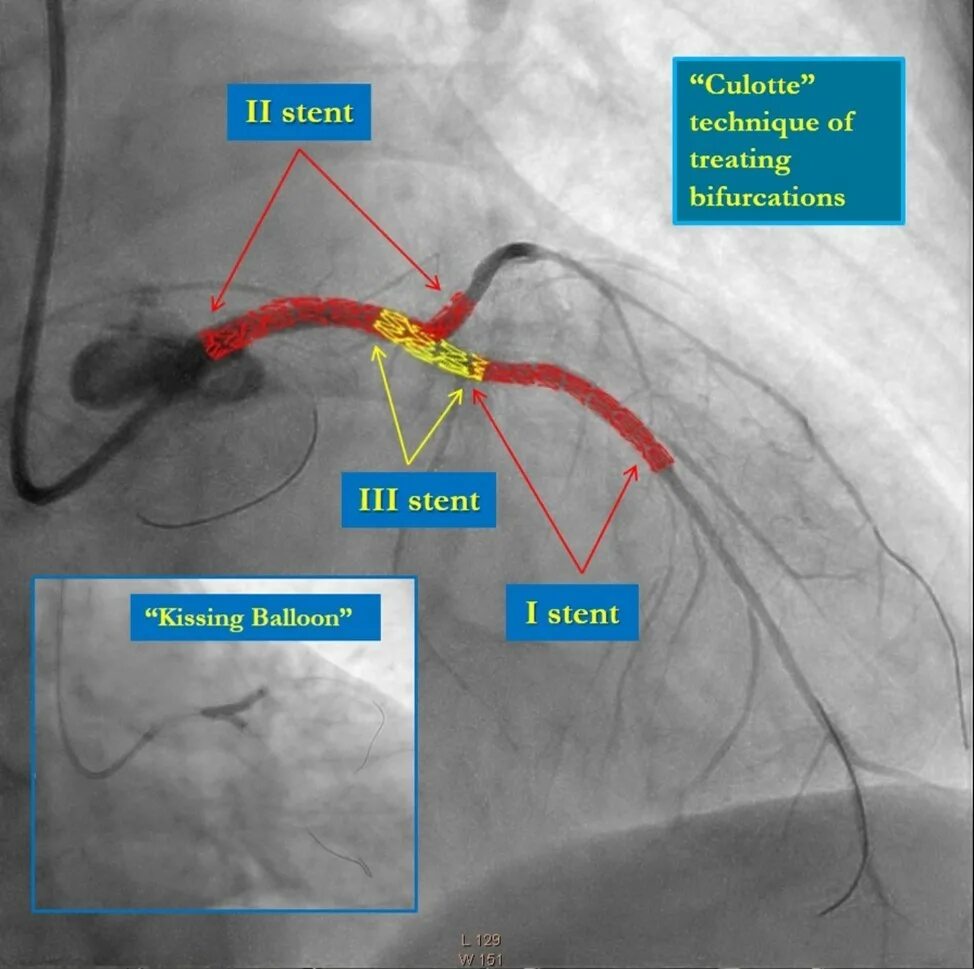

Стентирование самолет